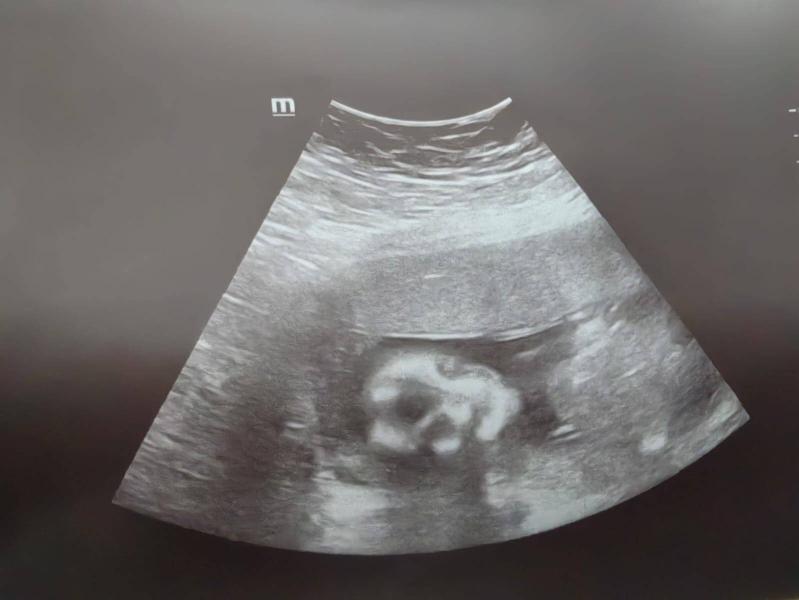

Первые фотки человечка🤗так и не узнали мы кто в "теремочке" живет, очень глубоко сидит и скромничает. Лежит, посасывает палец. Есть предположение что девочка, потому что отчетливого писюна не увидела, как это было у сына. Низкая плацентация сохраняется, перекрывает немного зев.

Девочка вероятнее всего на уз.